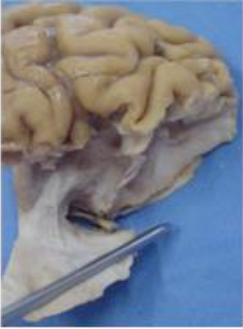

Figure 11: anatomical preparation, sagittal section.